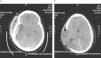

ResultadosSon un total de 14 pacientes que presentan hipertensión endocraneal secundaría a TCEG, 11 varones y 3 mujeres. La mediana de edad es de 14,5 años (rango 4–20 años). En la evaluación inicial presentaron un GCS con un rango entre 3–14 puntos. Las características de los pacientes antes de la CD se reflejan en la tabla 1. En todos se realizó un estudio por neuroimagen mediante TC en el momento de su ingreso en la UCIP. Las lesiones más frecuentes detectadas fueron las lesiones encefálicas difusas (LED) grados II y III que se presentaron en 4 casos cada una de ellas, lo que representa un 28,5% respectivamente. A todos los pacientes se colocó un sensor parenquimatoso para monitorizar la PIC a excepción del paciente 12 y todos presentaron cifras de hipertensión endocraneal mantenida, por encima de 25mmHg, a pesar del tratamiento antihipertensivo endocraneal del primer escalón terapéutico, y en 7 (50%) también tras tratamiento con coma barbitúrico. En todos los casos se realizó una CD para controlar las cifras de PIC y mejorar la PPC. Todas fueron unilaterales frontotemporoparietales con durotomía amplia, excepto el caso 1 en la que la CD fue frontal bilateral (fig. 1). La duramadre se dejó abierta en todos los casos y los defectos meningeos fueron recubiertos con Duraform (Codman, Johnson & Johnson, Raynham, MA., EE.UU.). El colgajo óseo fue desechado en todos los casos, dados los problemas relativos a su conservación, al riesgo de reabsorción y de pérdida de vitalidad del hueso que puede producirse hasta el momento de su reposición. En todos los pacientes, en los meses siguientes, se coloca material protésico de hidroxiapatita realizado a medida mediante TC tridimensional, fijado con tornillos y miniplacas de titanio. En 1 caso se practicó exéresis de focos contusitohemorrágicos con efecto masa (fig. 2).